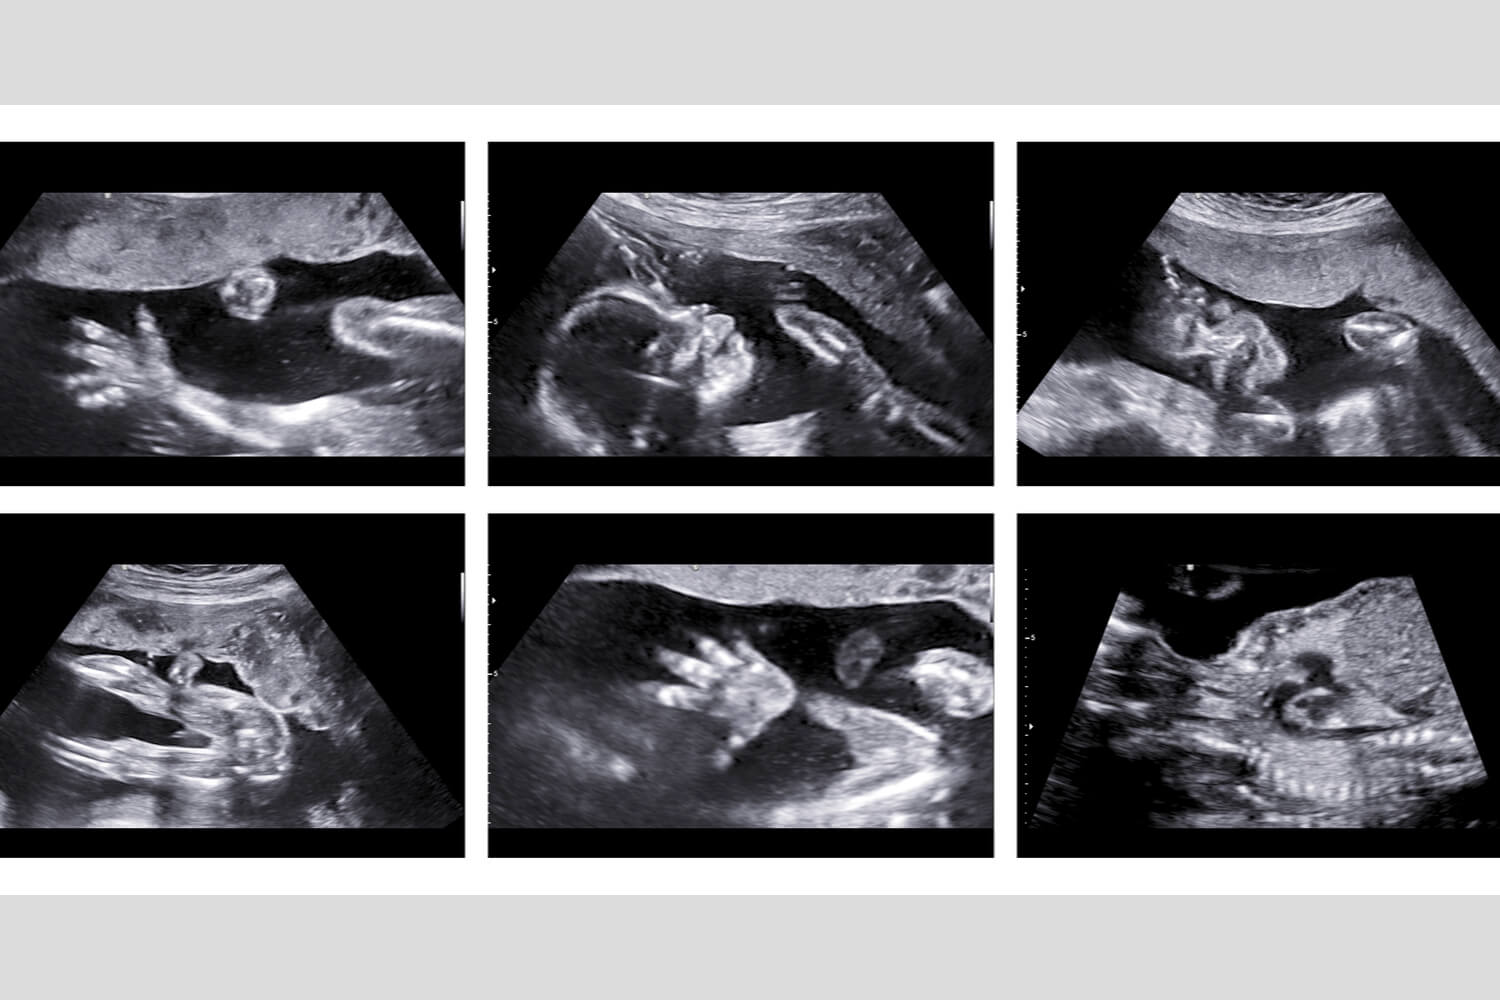

3d/4d sonography. Level 2 sonography. TIFFA scan. Anomalies scan Tiffa 3D Scan Cost It is the most important scan during the second trimester. The sonographer checks the baby's anatomy and examines any structural problem from head to toe. Learn about tiffa scan (targeted imaging for fetal anomalies), its uses, test results, procedures, and normal range during pregnancy. Tiffa scan centre is an institution specialising in performing all pregnancy screening necessary for monitoring the. Tiffa 3D Scan Cost.

TIFFA Scan MAA FETAL MEDICINE CENTRE Tiffa 3D Scan Cost The anomaly scan, is also referred to as a tiffa (targeted imaging for fetal anomalies), target or level ii scan. The anomaly scan or the tiffa scan examines the fetus from head to toe monitoring the overall growth, development, and health. It is the most important scan during the second trimester. Learn about tiffa scan (targeted imaging for fetal anomalies),. Tiffa 3D Scan Cost.

Twins TIFFA SCAN ultrasound TIFFA SCAN YouTube Tiffa 3D Scan Cost The sonographer checks the baby's anatomy and examines any structural problem from head to toe. It is the most important scan during the second trimester. A tiffa (targeted imaging for fetal anomalies) scan, also known as an anomaly scan, is typically performed during the second trimester of. The anomaly scan, is also referred to as a tiffa (targeted imaging for. Tiffa 3D Scan Cost.